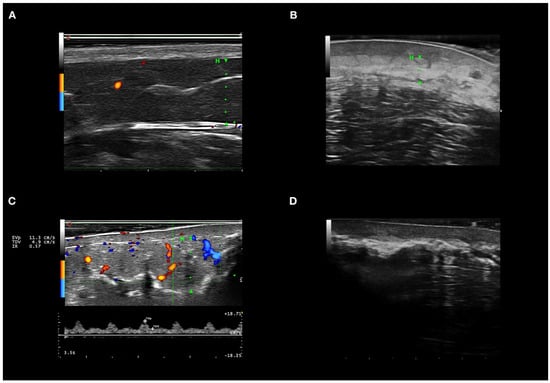

3.5. Ultrasound Features of Inflammation